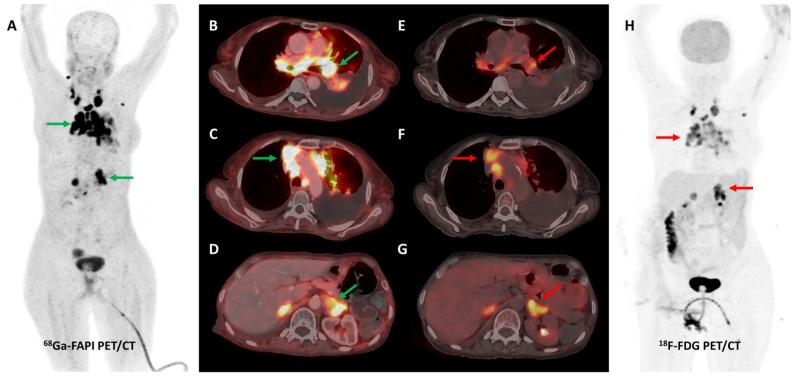

Despite revolutionizing the field of oncological imaging, Positron Emission Tomography (PET) with [F]Fluorodeoxyglucose (FDG) as its workhorse is limited by a lack of specificity and low sensitivity in certain tumor subtypes. Fibroblast activation protein (FAP), a type II transmembrane glycoprotein, is expressed by cancer-associated fibroblasts (CAFs) that form a major component of the tumor stroma. FAP holds the promise to be a pan-cancer target, owing to its selective over-expression in a vast majority of neoplasms, particularly epithelial cancers. Several radiolabeled FAP inhibitors (FAPI) have been developed for molecular imaging and potential theranostic applications. Preliminary data on FAPI PET/CT remains encouraging, with extensive multi-disciplinary clinical research currently underway. This review summarizes the existing literature on FAPI PET/CT imaging with an emphasis on diagnostic applications, comparison with FDG, pitfalls, and future directions.

尽管正电子发射断层扫描(PET)以[F]氟脱氧葡萄糖(FDG)作为其主要显像剂,彻底改变了肿瘤影像学领域,但在某些肿瘤亚型中,它存在特异性不足和灵敏度较低的局限性。成纤维细胞活化蛋白(FAP)是一种II型跨膜糖蛋白,由构成肿瘤基质主要成分的癌症相关成纤维细胞(CAF)表达。由于FAP在绝大多数肿瘤,尤其是上皮癌中选择性过度表达,它有望成为一种泛癌靶点。已经开发了几种放射性标记的FAP抑制剂(FAPI)用于分子成像和潜在的诊疗应用。FAPI PET/CT的初步数据仍然令人鼓舞,目前正在进行广泛的多学科临床研究。这篇综述总结了关于FAPI PET/CT成像的现有文献,重点是诊断应用、与FDG的比较、陷阱和未来方向。